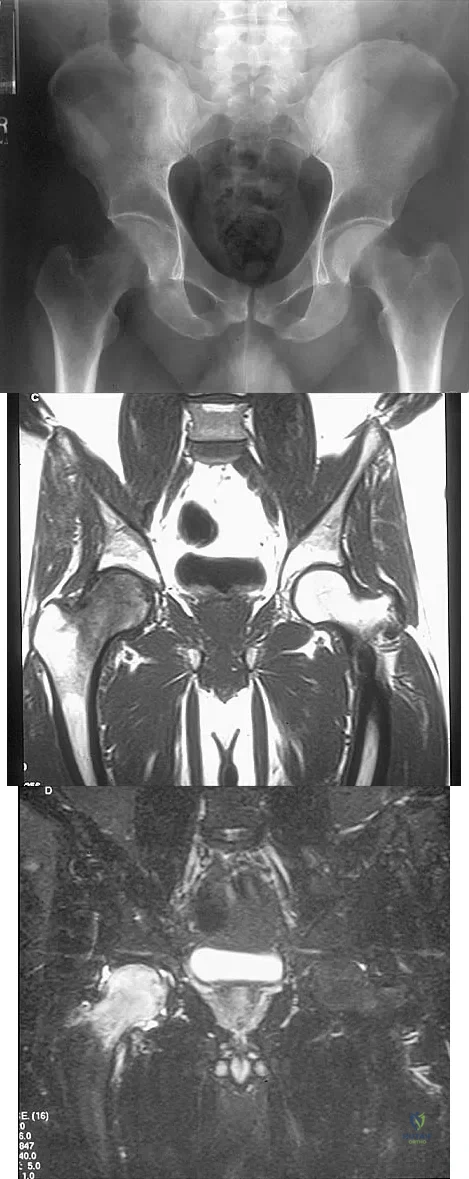

A 22-year-old man has mild hip pain bilaterally and multiple skeletal lesions. Based on the pelvic radiograph shown in Figure 30, what is the inheritance pattern for his disorder?

A 9-year-old child has right groin pain after falling from a tree. Examination reveals that the right leg is held in external rotation, and there is significant pain with attempts at passive range of motion. Radiographs are shown in Figures 43a and 43b. Management should consist of

Figures 10a through 10c show the plain radiograph and MRI scans of a 41-year-old man who has right hip pain. What is the most likely diagnosis?